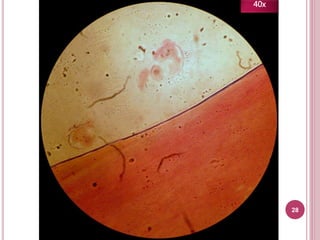

28

40x

Características

 Protoescólex suelto

 Protoescólex flotando

en líquido hidatídico

En el laboratorio SÓLO hay arenilla

hidatidica de E. granulosus